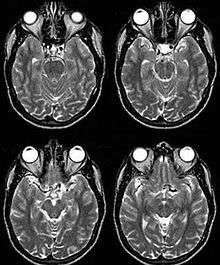

Internal Carotid Artery dolichoectasia is particularly interesting because the artery normally already contains one hairpin turn. Seen in an MRI as two individual arteries at this hairpin, a carotid artery dolichoectasia can progress so far as to produce a second hairpin turn and appear as three individual arteries on an MRI. In the case of a dolichoectasia of the Internal Carotid Artery (ICD), the pathogenesis is primarily related to compression of the Optic Nerves at the Optic Chiasma (see Fig. 1 and 2).